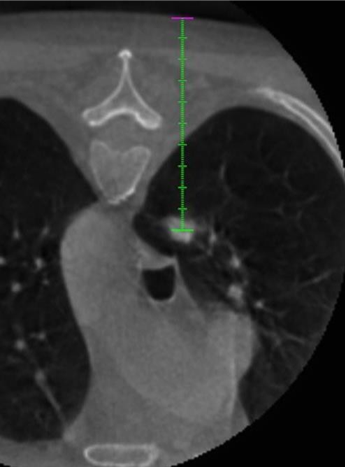

3. 基于融合的PET-CBCT数据,计划穿刺针路径指向PET-高代谢的目标

4. 基于这一计划,活检针被定位在实时反馈与目标解剖和配准代谢活动的关系。

5. 使用相同的成像融合方案获得CBCT数据来确认针的定位。

PET-CBCT的融合图像也可以考虑。CBCT可以通过现代血管造影系统获取CT横断面图像。结合专用的软件,使其成功地应用于指导经皮活检。 ![]() 通过工作站把先前患者的PET与CBCT的图像融合进行CBCT引导下的肺活检

通过CBCT经胸经皮肺活检是一种安全且有用的鉴别肺结节的方法。在大多数情况下,在怀疑肺癌的组织学诊断是必要的,以进行靶向治疗和寻找特定的突变。特别是,由融合图像18F-FDG-PET/CBCT提供的解剖和代谢信息提高了组织学诊断的准确性,降低了假阴性的数量和增加获得最终解剖病理诊断的概率。

1. 术前CBCT扫描

规划与虚拟导航软件

2. 确认CBCT

3. 术后CBCT